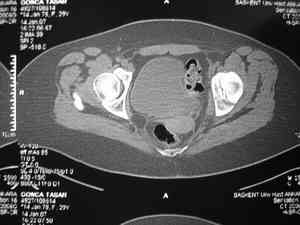

Dear group, 30 years age female MVA front seat, head trauma + post column left acetabular fracture, 2.5 weeks skeletal traction. She is now conscious but still confused without any surgical treatment for brain edema.

Latest X rays and CAT is attached. Fracture within first 1.5 cm from the weight bearing dome, although AP and Obtrator oblique good, iliac oblique view reveals some displacement. I'm not sure that nonsurgical treatment will be OK Hüseyin Demirors Baskent University Dept of Orthopedics and Travmatology Ankara TURKEY